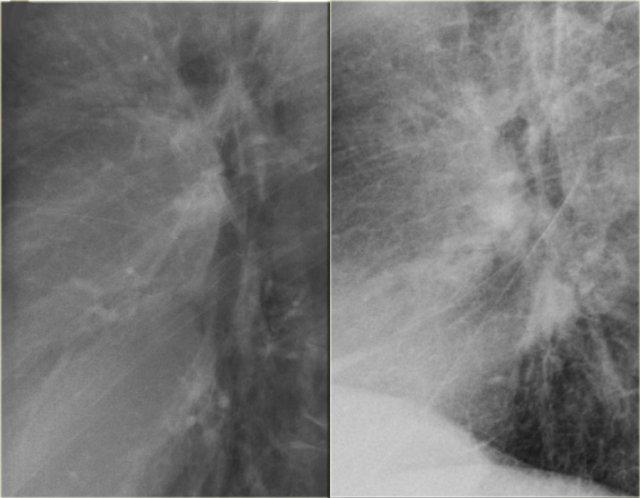

Bên trái là hình ảnh bệnh nhân suy tim sung huyết.

Có sự tăng khẩu kính của các mạch máu phổi và chúng mất nét bờ do bị bao quanh bởi phù nề.

X-quang ngực bình thường trước đó (trái) và suy tim sung huyết giai đoạn II với mờ quanh rốn phổi (phải)

Bên trái là hình ảnh một bệnh nhân khác bị suy tim sung huyết.

Tư thế chụp nghiêng thể hiện rõ sự tăng đường kính của các mạch máu phổi và bờ mờ nhạt của chúng.

Lưu ý cũng có các đường vách và mô kẽ nổi bật.

Ngoài ra, khe liên thùy lớn dày lên rõ rệt.